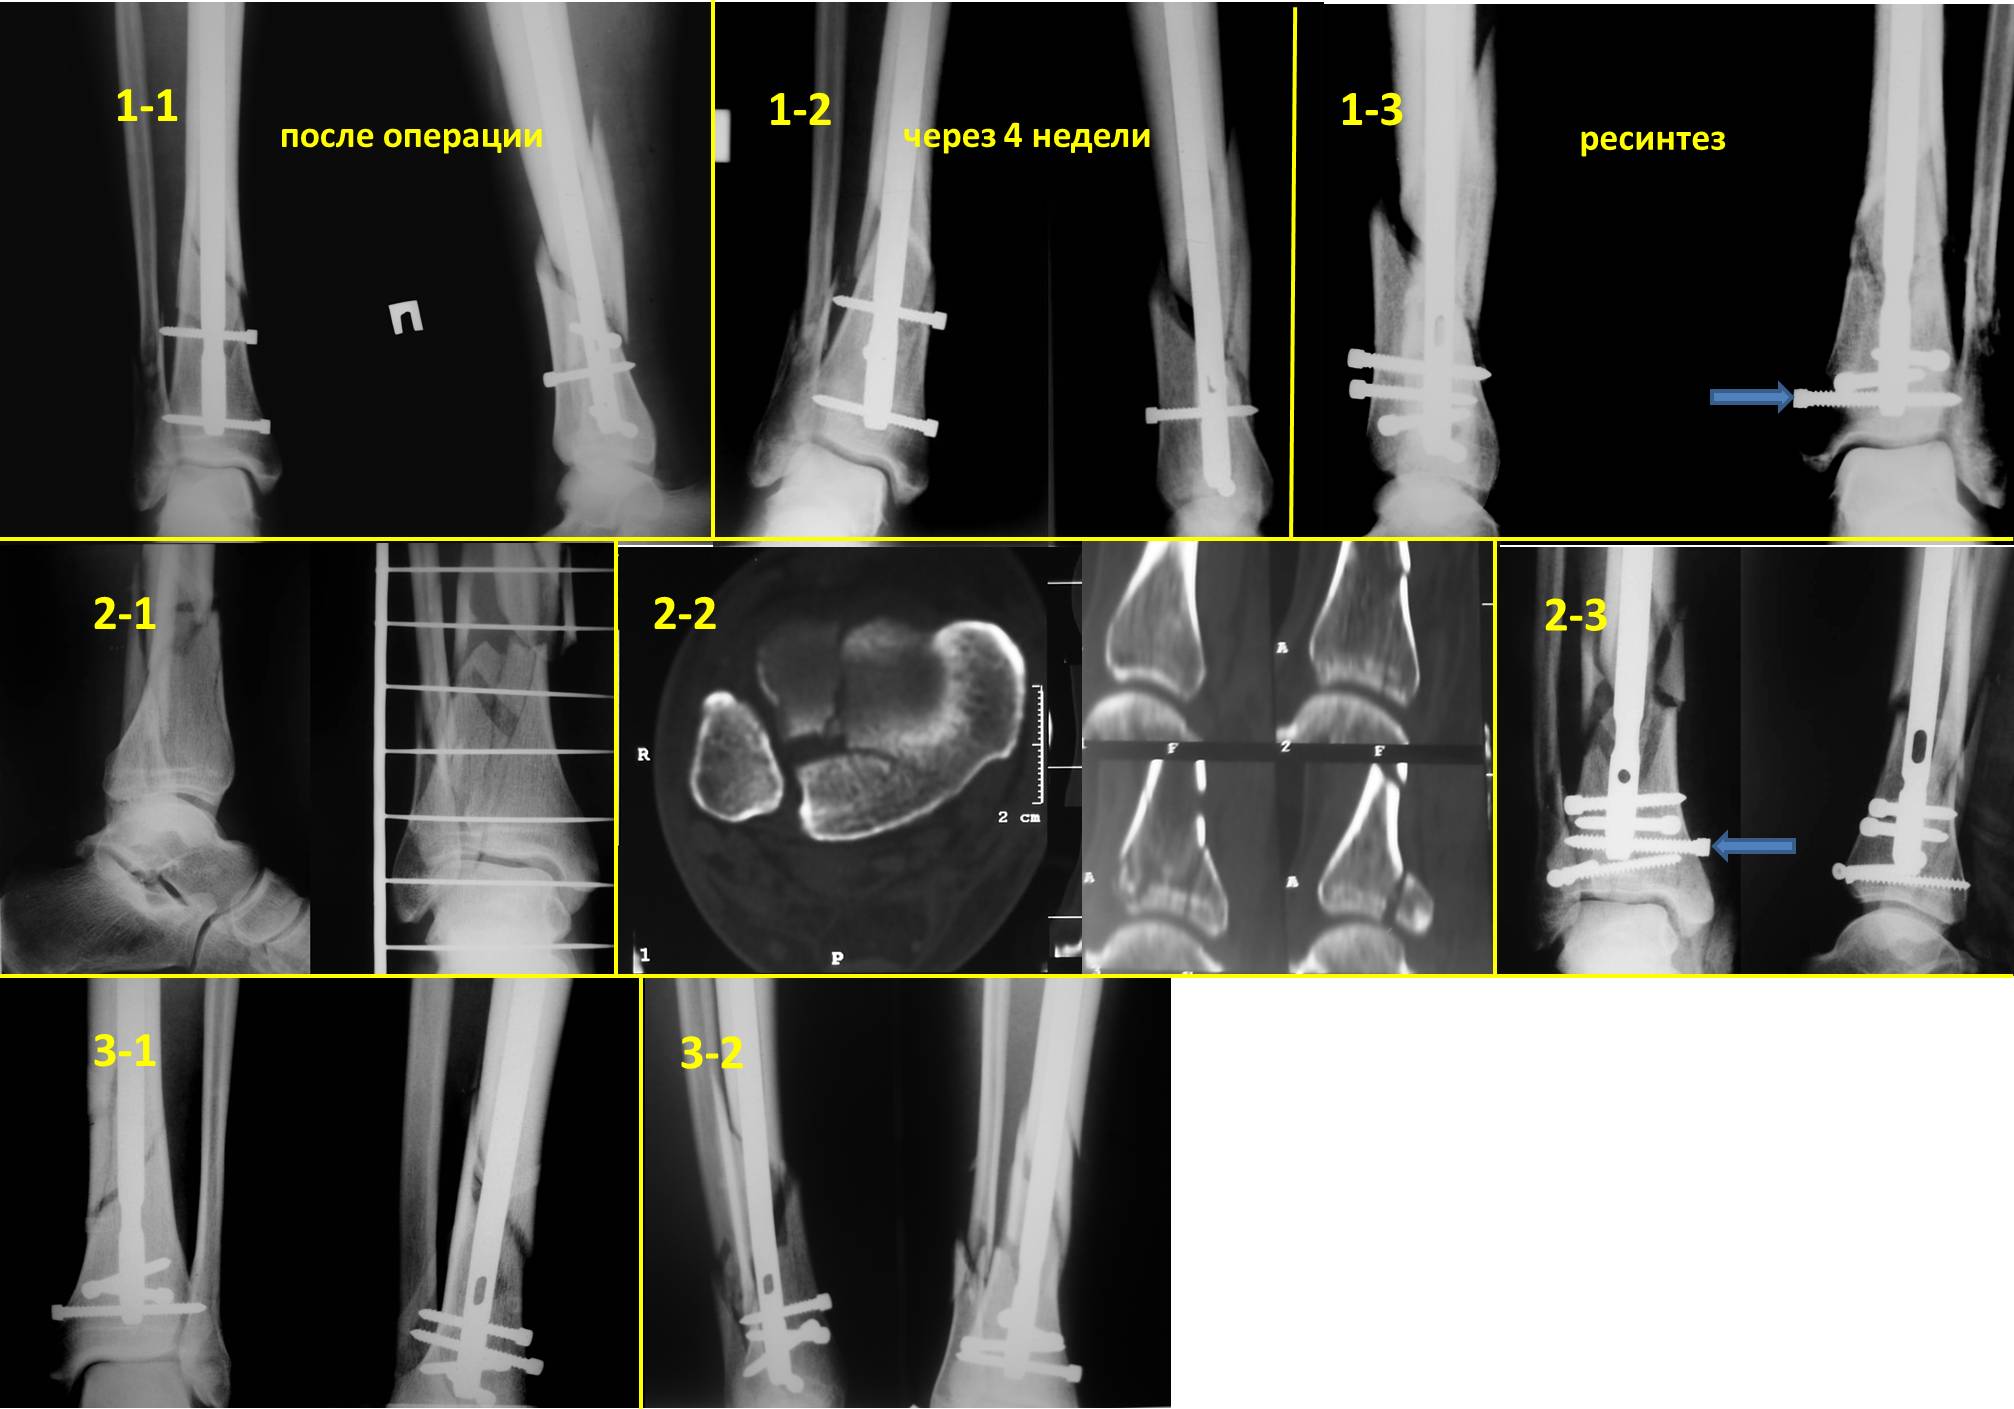

Очень интересная тема – дистальное блокирование при инфраистмальных переломах. К сожалению, аргументировано её осветить не представляется возможным в жёстких рамках поста. С моей точки зрения, неадекватное дистальное блокирование при инфраистмальных переломах большеберцовой кости является наиболее частой причиной неудач при интерлокинге. Можно ожидать проблем, если блокирование таких переломов выполняется только во фронтальной плоскости. Даже третий блокирующий винт, проведенный в сагиттальной плоскости, не всегда гарантирует необходимую стабильность (пример 1-1 – 1-3 во вложенном файле). Нестабильность фиксации случается, как правило, из-за того, что диаметр блокирующих винтов меньше диаметра блокирующих отверстий стержня, что позволяет блокирующим винтам (а значит и дистальному отломку) отклонятся от перпендикулярного положения относительно стержня. Чем больше разница в диаметрах, тем больше угол возможного отклонения. Несколько большую стабильность обеспечивают блокирующие винты, заворачивающиеся в стержень (отмечены стрелками). Мы для себя взяли за правило выполнять дистальное блокирование всех инфраистмальных переломов минимум тремя винтами, проведенными в разных плоскостях (пример 2-1 – 2-3 во вложенном файле). А с учётом того что мы не ограничиваем нагрузку в послеоперационном периоде  и с целью уменьшения вероятности перелома блокирующих винтов при нагрузке - стандартная процедура дистального блокирования состоит во введении четырёх блокирующих винтов введенных в разных плоскостях (пример 3-1 – 3-2 во вложенном файле). После применения такой методики не отмечено случаев несращения после интерлокинга инфраистмальных переломов.